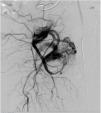

Presentamos el caso de un varón de 47 años de edad, sin antecedentes médicos ni quirúrgicos de interés, salvo hernia de hiato con espasmos esofágicos ocasionales. Acudió a su médico de atención primaria por clínica de dolor tipo ciático irradiado hacia la pierna derecha y la región perineal, acompañado de parestesias de semanas de evolución, sin traumatismo previo. Se le realizó una radiografía simple de columna, donde se objetivó un aumento de densidad en la zona anatómica de la vejiga. Se le solicitó una RMN lumbosacra con diagnóstico de mínima discopatía degenerativa lumbar y lesión redondeada adyacente al psoas derecho, de posible origen renal, junto con masas lobuladas a nivel pélvico. Ante estos hallazgos, y con la sospecha clínica de tumor vesical, se remitió a urología. En la consulta especializada se le realizó una ecografía abdominal detectándose una masa polilobulada paravesical derecha, vascularizada y parcialmente calcificada, sin poder concretar la etiología de la misma. Ante estos hallazgos se le solicitó una RMN pélvica donde se identificó una lesión tubular muy vascularizada de gran tamaño 13,3×12,2×6,1cm (craneocaudal, anteroposterior y transversal respectivamente) que desplazaba la vejiga, la próstata, las vesículas seminales y la región anorrectal. Se describió la presencia de dilatación de estructuras venosas adyacentes. Se remitió a la consulta de cirugía vascular para valoración. La exploración física del paciente fue anodina, con pulsos presentes a todos los niveles y sin masa abdominal pulsátil. Se le realizó un angioTAC con contraste donde se apreció una dilatación aneurismática fusiforme de 54×53,2×74,8mm (craneocaudal, transverso y anteroposterior) que comenzaba en la arteria iliaca interna derecha y se extendía inferiormente hacia la pelvis (fig. 1). Con sospecha diagnóstica de aneurisma hipogástrico derecho se le pidió arteriografía, diagnosticándose de MAV de alto flujo con aporte arterial de las arterias vesicales y drenaje venoso por venas pudendas hasta la iliaca interna. El drenaje venoso presentaba 2 estenosis (fig. 2).

Se decidió tratamiento quirúrgico por vía endoluminal mediante embolización de la MAV tras cateterización selectiva de la arteria hipogástrica derecha, vía femoral derecha, y venosa femoral contralateral. En la primera inyección de contraste diagnóstica se objetivó gran disminución del tamaño del nidus con trombosis casi completa del mismo, por lo que se procedió a la colocación de un coil Concerto® de 5×20 en la arteria aferente y Onyx en la zona residual. En el examen final se objetivó excelente control morfológico del procedimiento con trombosis del nidus.